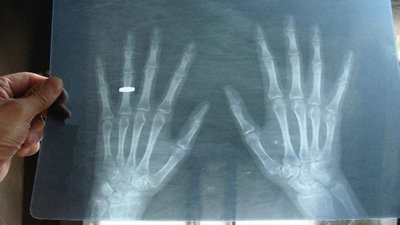

无明显诱因,于老师出现双手掌指、指间关节肿痛,屈伸不利,病情逐渐加重并出现四肢多处关节肿痛,活动不利,在诊所中诊断为受凉所引起的风湿性关节炎,配了些口服药就一直吃着。在接下来的几年时间里,于老师备受疼痛折磨:全身多处关节红肿疼痛,手掌僵硬异常,手指有些弯曲变形,轻压腕部神经还会出现手部麻木、疼痛和无力等症状,诊所里给的药也没有断过,可他的病还是一天天的加重。最后来到我院接受正规治疗。

(图:于老师的双手已严重变形)